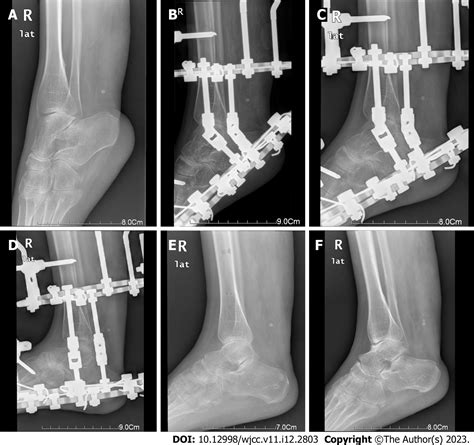

When conservative measures like custom footwear or physical therapy fail to provide adequate relief, surgery becomes the gold standard. The choice of surgery depends on the severity of the rigidity and the patient’s activity level.

• Tendon Lengthening: Addressing tight structures like the Achilles tendon to allow for better heel strike during gait.

• Osteotomy: Surgically cutting and repositioning the bones of the foot to create a more stable, plantigrade position.

• Arthrodesis (Fusion): In severe cases of joint degeneration, fusing the affected bones together eliminates pain by removing motion from the arthritic joint.

Post-operative recovery is a significant phase of the treatment journey. Patients must adhere to a strict rehabilitation protocol to regain strength and ensure proper healing of the bones and soft tissues. This typically involves a period of non-weight-bearing movement, followed by gradual transition to specialized shoes or braces under the guidance of a physical therapist.

💡 Note: Success in adult clubfoot surgery is defined by achieving a pain-free, stable foot capable of supporting weight, rather than achieving a perfectly aesthetic foot shape.